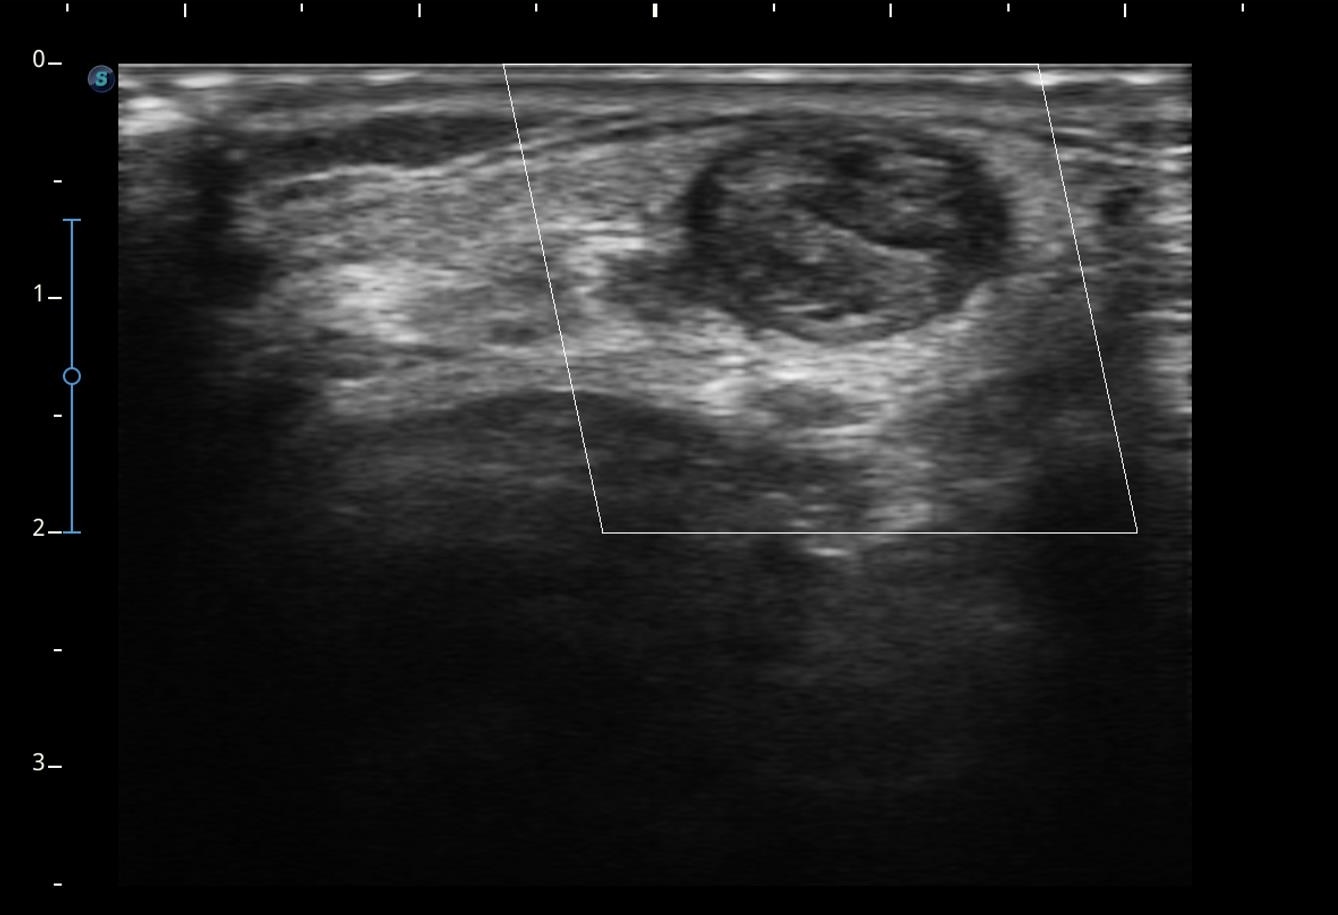

Se realiza ecografía clínica objetivándose ausencia de flujo en el interior de la luz, con imagen ecogénica en el interior compatible con trombo, no colapsándose a la presión con el transductor.

Sospechamos de trombosis venosa yugular externa (VYE). Se deriva a servicio de Urgencias para completar estudio.

Se realiza analítica de sangre (Dímero D 2029 ng/ml) y radiografía de tórax anodina. Se realiza eco-doppler cervical observándose trombosis de vena yugular externa izquierda al menos hasta su confluencia yugulosubclavia. Vena yugular izquierda no visualizada. Venas subclavia, axilar y braquiales izquierdas permeables sin datos de trombosis.

Se confirma nuestra sospecha diagnóstica: obstrucción total venosa central (OTVC) trombótica de la vena yugular externa.